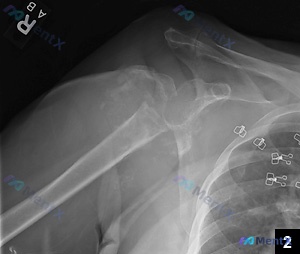

整理到一份右侧上肢(肩关节至肱骨远端)的X光影像资料及初步分析,先把核心表现列出来,想听听大家的判断思路: 关键影像表现 1. 局部损伤: - 肱骨近端(大结节、肱骨头、外科颈区域)可见骨皮质中断、碎裂,骨折线延伸,有明显成角和移位; - 盂肱关节对位关系紊乱,有脱位/半脱位征象; - 肱骨远端(髁...

整理了一个有点意思、甚至有点“矛盾”的骨科病例,先把基础信息放出来: 基础情况:62岁女性,因持续性肩部疼痛求医。 关键矛盾点:她明确报告没有近期或过去的外伤史、感染史。 影像初步结果:右肩部X光提示—— - 肱骨近端复杂性骨折:累及解剖颈及大结节,伴有明显移位和多发骨折碎片 - 盂肱关节脱位:肱骨...